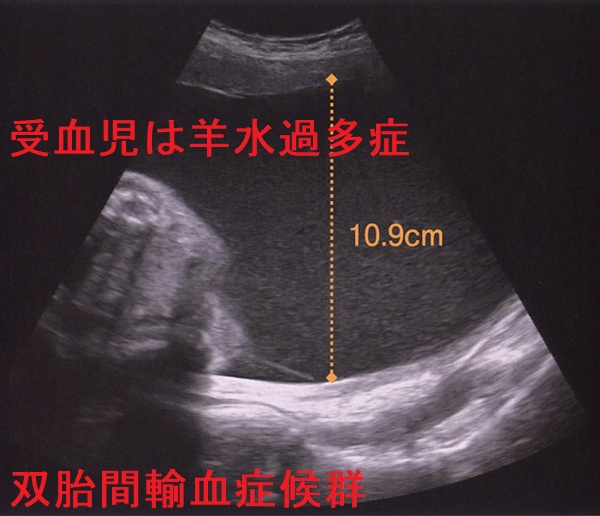

双胎間輸血症候群(そうたいかんゆけつしょうこうぐん:Twin-to-twin transfusion syndrome:TTTS)は、一卵性双胎児が1つの胎盤を共有し(1胎盤2羊膜、1絨毛2羊膜)、栄養血管が一部つながっている(吻合血管)ためにおこります。胎児への血液供給は不均等になり、胎盤血流が多い児と少ない児に分かれ異常な発育を来します。

血液を多くもらう児(受血児)は、循環血液量が増えて

- 腎血流量も増加→羊水過多症

- うっ血性心不全

血液が盗られ胎盤血流が少ない児(供血児)は、

- 発育不全・肺低形成

- 低血糖

- 腎血流量が減少→羊水過少症、腎不全起き

、どちらも正常な発育が望めません。

双胎間輸血症候群(TTTS)も妊娠時一過性甲状腺機能亢進症の原因となります。合併症のない双子妊娠と比較して、hCG値は有意に高く、妊娠時一過性甲状腺機能亢進症を起こしやすい[Eur J Obstet Gynecol Reprod Biol. 2009 Jun;144(2):124-9.]。

その理由として考えられるのは、胎盤容積増大と供血児の胎盤低酸素症です。

レーザー療法が有効であった場合、hCG濃度は著しく低下し、甲状腺ホルモン(FT3,FT4)値もそれに伴って徐々に減少します。(Endocr J. 2015;62(10):949-52.)[Front Endocrinol (Lausanne). 2021 Jul 16;12:705567.]